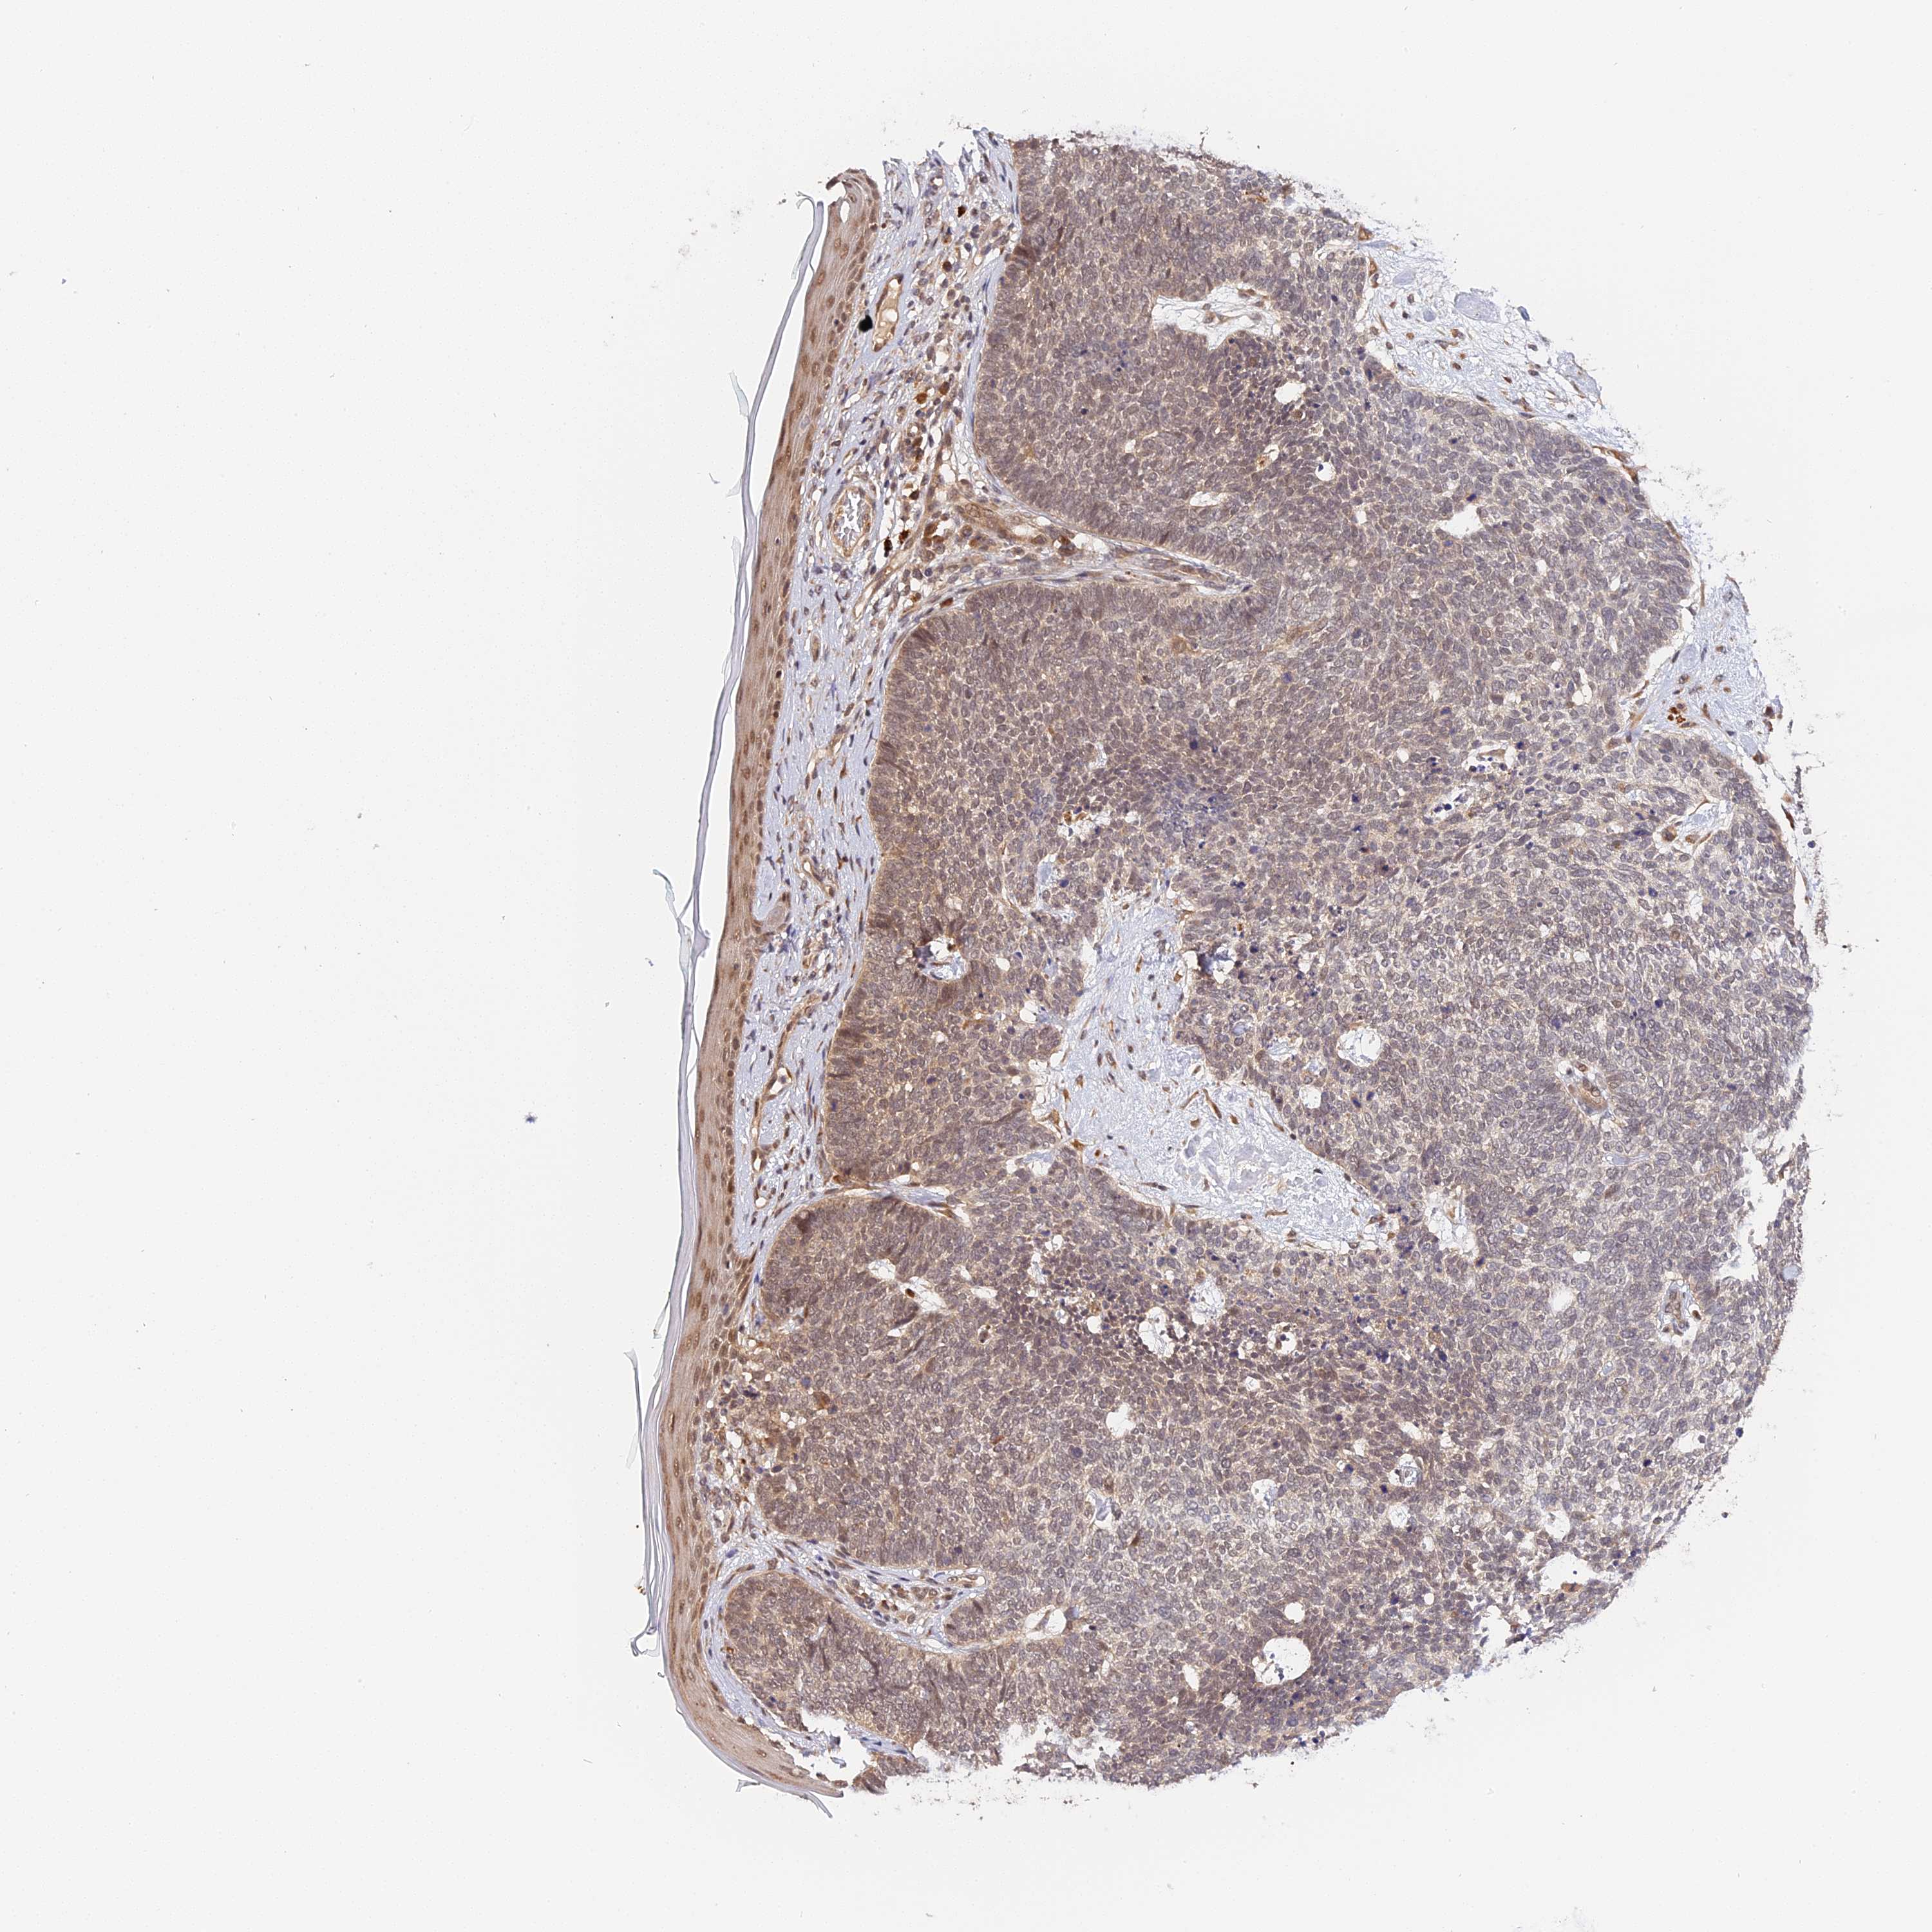

SKIN CANCER - Protein expressioni

A mouse-over function shows sample information and annotation data. Click on an image to view it in a full screen mode. Samples can be filtered based on level of antibody staining by selecting one or several of the following categories: high, medium, low and not detected. The assay and annotation is described here.

Antibody stainingi

Antibody staining in the annotated cell types in the current human tissue is reported as not detected, low, medium, or high, based on conventional immunohistochemistry profiling in selected tissues. This score is based on the combination of the staining intensity and fraction of stained cells.

Each image is clickable and will lead to virtual microscopy that enables deeper exploration of all samples and also displays staining intensity scores, fraction scores and subcellular localization as well as patient and tissue information for each sample.

Antibody HPA041045

Antibody HPA041968

Staining

High

Medium

Low

Not detected

Squamous cell carcinoma, NOS

Basal cell carcinoma